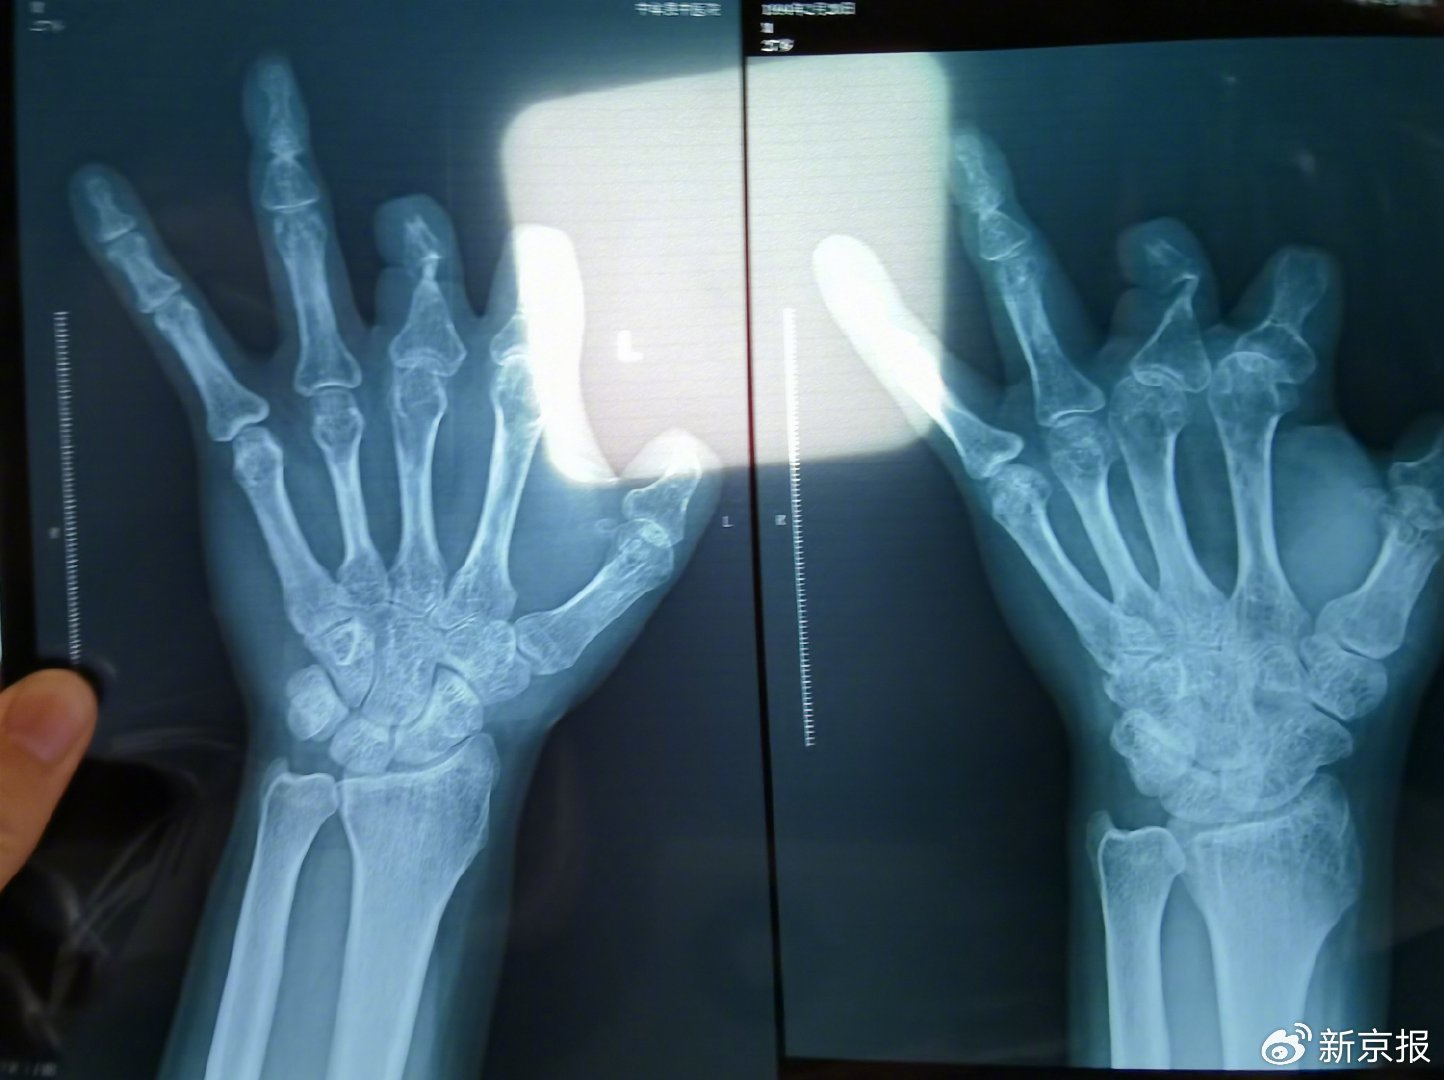

单𱖧.68万元,声称在术中植入体内、用于缝合血管的两个环形吻合装置,却在患者的X光片上消失了,原因竟是“手术时没有使用”。

2021月,患者彭先生拍摄的左手X光片,未见收费单据中列出的微血管吻合装置。新京报记者 程亚龙 摄

作为一名三甲医院的副主任医师,王福建的所作所为令人瞠目结舌,寒心透顶。医者本应救死扶伤,关怀患者,他却利用患者对医生的信任、对健康的渴求,将手术台变成行骗舞台,把他人病痛当成了敛财机会。根本用不上的昂贵器材,他能一口气给患者开𰱪个,然后扔进垃圾桶白白浪费。甚至为了规避投诉,他还将本应用于缝合血管的装置,缝在患者血管旁边的肉里,只为在X光下“留痕”。